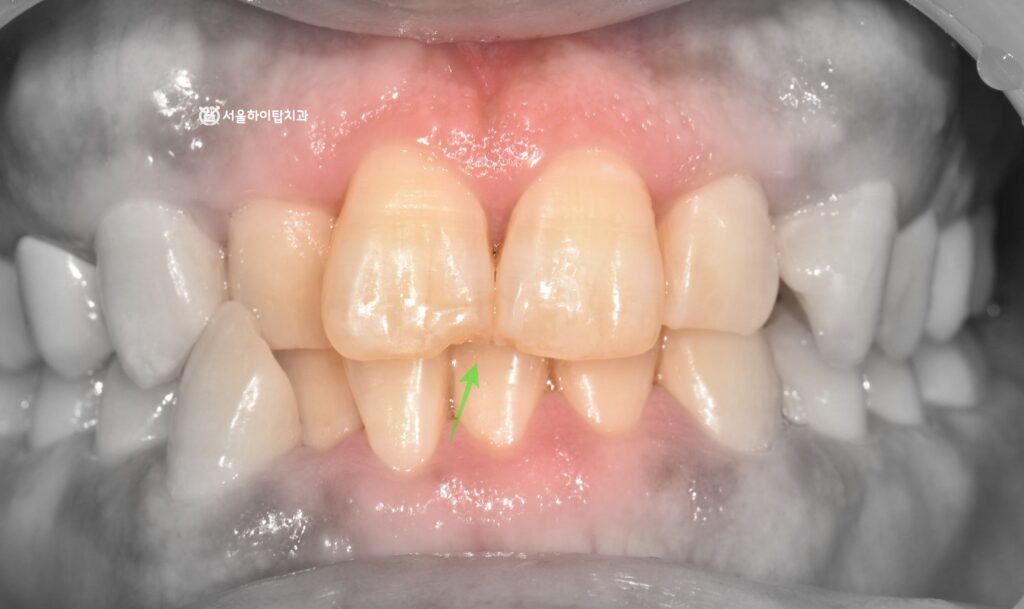

또한 구강 내 모습을 다시 한 번 살펴보면,

교정적인 관점에서 치아들이 고르게 배열되지 않은 총생 상태를 확인할 수 있으며

일부 앞니에서는 반대로 물리는 반대교합 양상도 함께 보입니다.

이처럼 치아 배열이 고르지 않거나 부정교합이 존재하는 경우,

교합 시 특정 치아에 비정상적인 힘이 집중될 수 있기 때문에

앞니 절단연 부위의 파절에 간접적인 원인이 될 수 있습니다.

다만 현재 파절은 절단면에 국한된 비교적 작은 범위의 손상으로

치아의 구조적인 손상이 크지 않은 상태입니다.